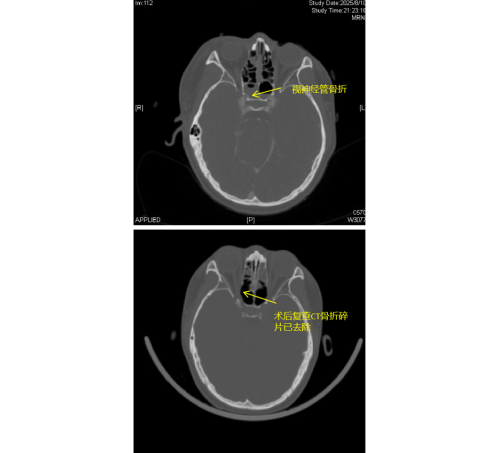

患者李琦(化名)是一名17岁少年,夜间骑电动车不慎撞上路边栏杆,随即出现右眼视力骤降、头痛头晕等症状,被120紧急送入香港马会app (南华大学附属香港马会app )急诊科。经检查发现,李琦存在颅底多处骨折、面颅多发骨折,尤其危急的是右侧视神经管骨折,碎裂的骨片直接压迫视神经及邻近的颈内动脉,导致右眼瞳孔散大、对光反射消失,视力完全丧失,病情极为危重。

由于视神经管周围解剖结构复杂,上方毗邻前颅底,下方紧邻颈内动脉和海绵窦,稍有不慎就可能导致脑脊液鼻漏、视神经断裂甚至颈内动脉破裂出血等严重后果,因此视神经的特殊位置被视为“手术雷区”。加之操作空间小,手术难度大,对于医生而言是一个巨大的挑战。视神经与鼻窦相邻,用鼻内镜经鼻窦进行视神经管减压手术,视野清楚、损伤最小。在手术过程中,康晓明医生利用高清鼻内镜,精准地清除了压迫视神经的骨折碎片,有效降低了神经压力。

手术完成后即刻观察到李琦右眼对光反射恢复灵敏,经过系统的治疗,其右眼视力已恢复至0.1,术后效果显著。目前,李琦正在进一步康复治疗中。此类高难度手术的成功,不仅展现了医院在多学科协作和急重症救治方面的综合实力,也为复杂颅底外伤患者带来了新的希望。